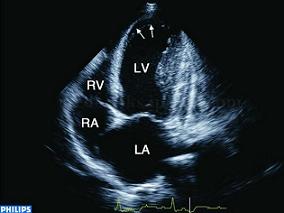

1小时条评论【病例1】 病例和相关检查 患者,男性,44岁,心悸、乏力、胸部不适1年余,进行性加重,近期出现活动气短,呼吸困难等症状。查体:心界增大,肝大,双下肢水肿,心脏听诊闻及第三及第四心音,偶发心律不齐。血压正常。X线检查:心影明显扩大,肺淤血。 超声图片 如...